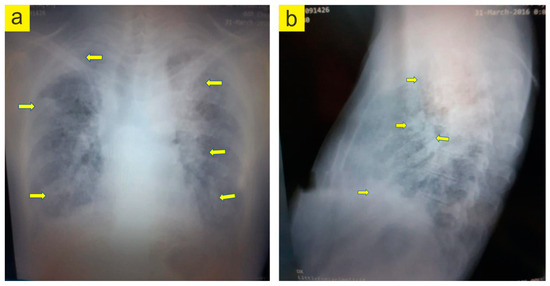

- Gupta, N.; Finlay, G.A.; Kotloff, R.M.; Strange, C.; Wilson, K.C.; Young, L.R.; Taveira-DaSilva, A.M.; Johnson, S.R.; Cottin, V.; Sahn, S.A.; et al. Lymphangioleiomyomatosis Diagnosis and Management: High-Resolution Chest Computed Tomography, Transbronchial Lung Biopsy, and Pleural Disease Management. An Official American Thoracic Society/Japanese Respiratory Society Clinical Practice Guideline. Am. J. Respir. Crit. Care Med. 2017, 196, 1337–1348. [Google Scholar] [CrossRef] [PubMed]